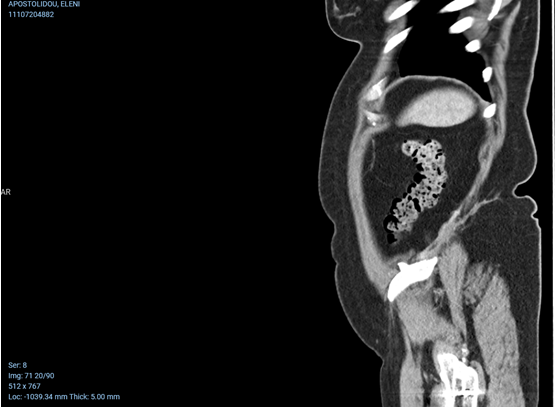

CT άνω κοιλίας με σκιαγραφικό που αναδεικνύει συστάδα διατεταμένων ελίκων λεπτού εντέρου στο κέντρο δίνοντας εικόνα κουνουπιδιού (βέλη) (Ευγενική παραχώρηση Dr. V. Penopoulos)